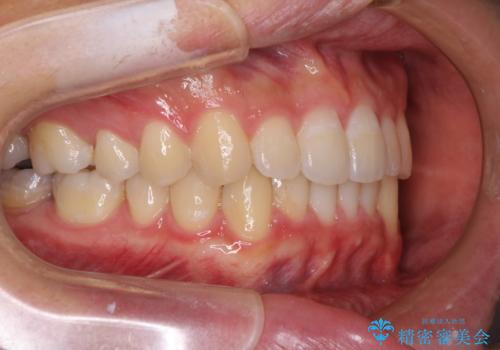

口が少し閉じにくい インビザラインによる非抜歯矯正

- インビザライン

- 口元の突出感を治したいとのことで来院された患者様です。

上下顎ともにIPR(歯と歯の間を削る)と歯列全体の拡大によって口元が引っ込むように設計し、インビザラインにより治療を行うこととしました。

抜歯をして口元を下げなければならないほど出っ歯ではなかったため、少しずつ治療ゴールを変更しながら仕上げていきました。

気になっていた前歯の飛び出した印象は、最終的にはスッキリと引っ込み、大変満足していただきました。